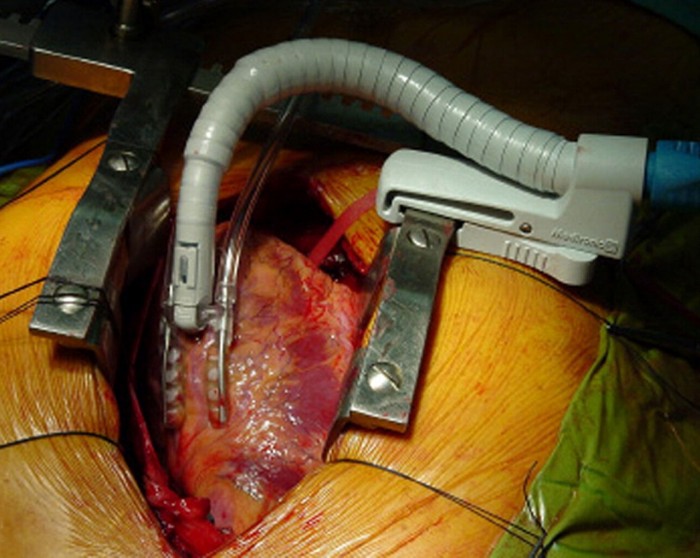

3 Coronary Revascularization:

It is known as coronary artery bypass grafting as it is an operation redirects the blood around one or more blocked coronary arteries to develop blood flow to the heart. Original connections are done via arteries or vein grafts from other parts of the patient’s body. Patients whose ventricular utility is deteriorating too rapidly, are not recommended to have this operation as the dangers are too elevated.

2 Surgical Ventricular Restoration:

This surgery is done to cure congestive heart failure due to a heart attack to develop its function by getting it to its regular size and shape. It is very risky as the patient is placed on the heart-lung machine. Upgrading in techniques has been done and the hospital readmission rate for a SVR is merely 8.8%.